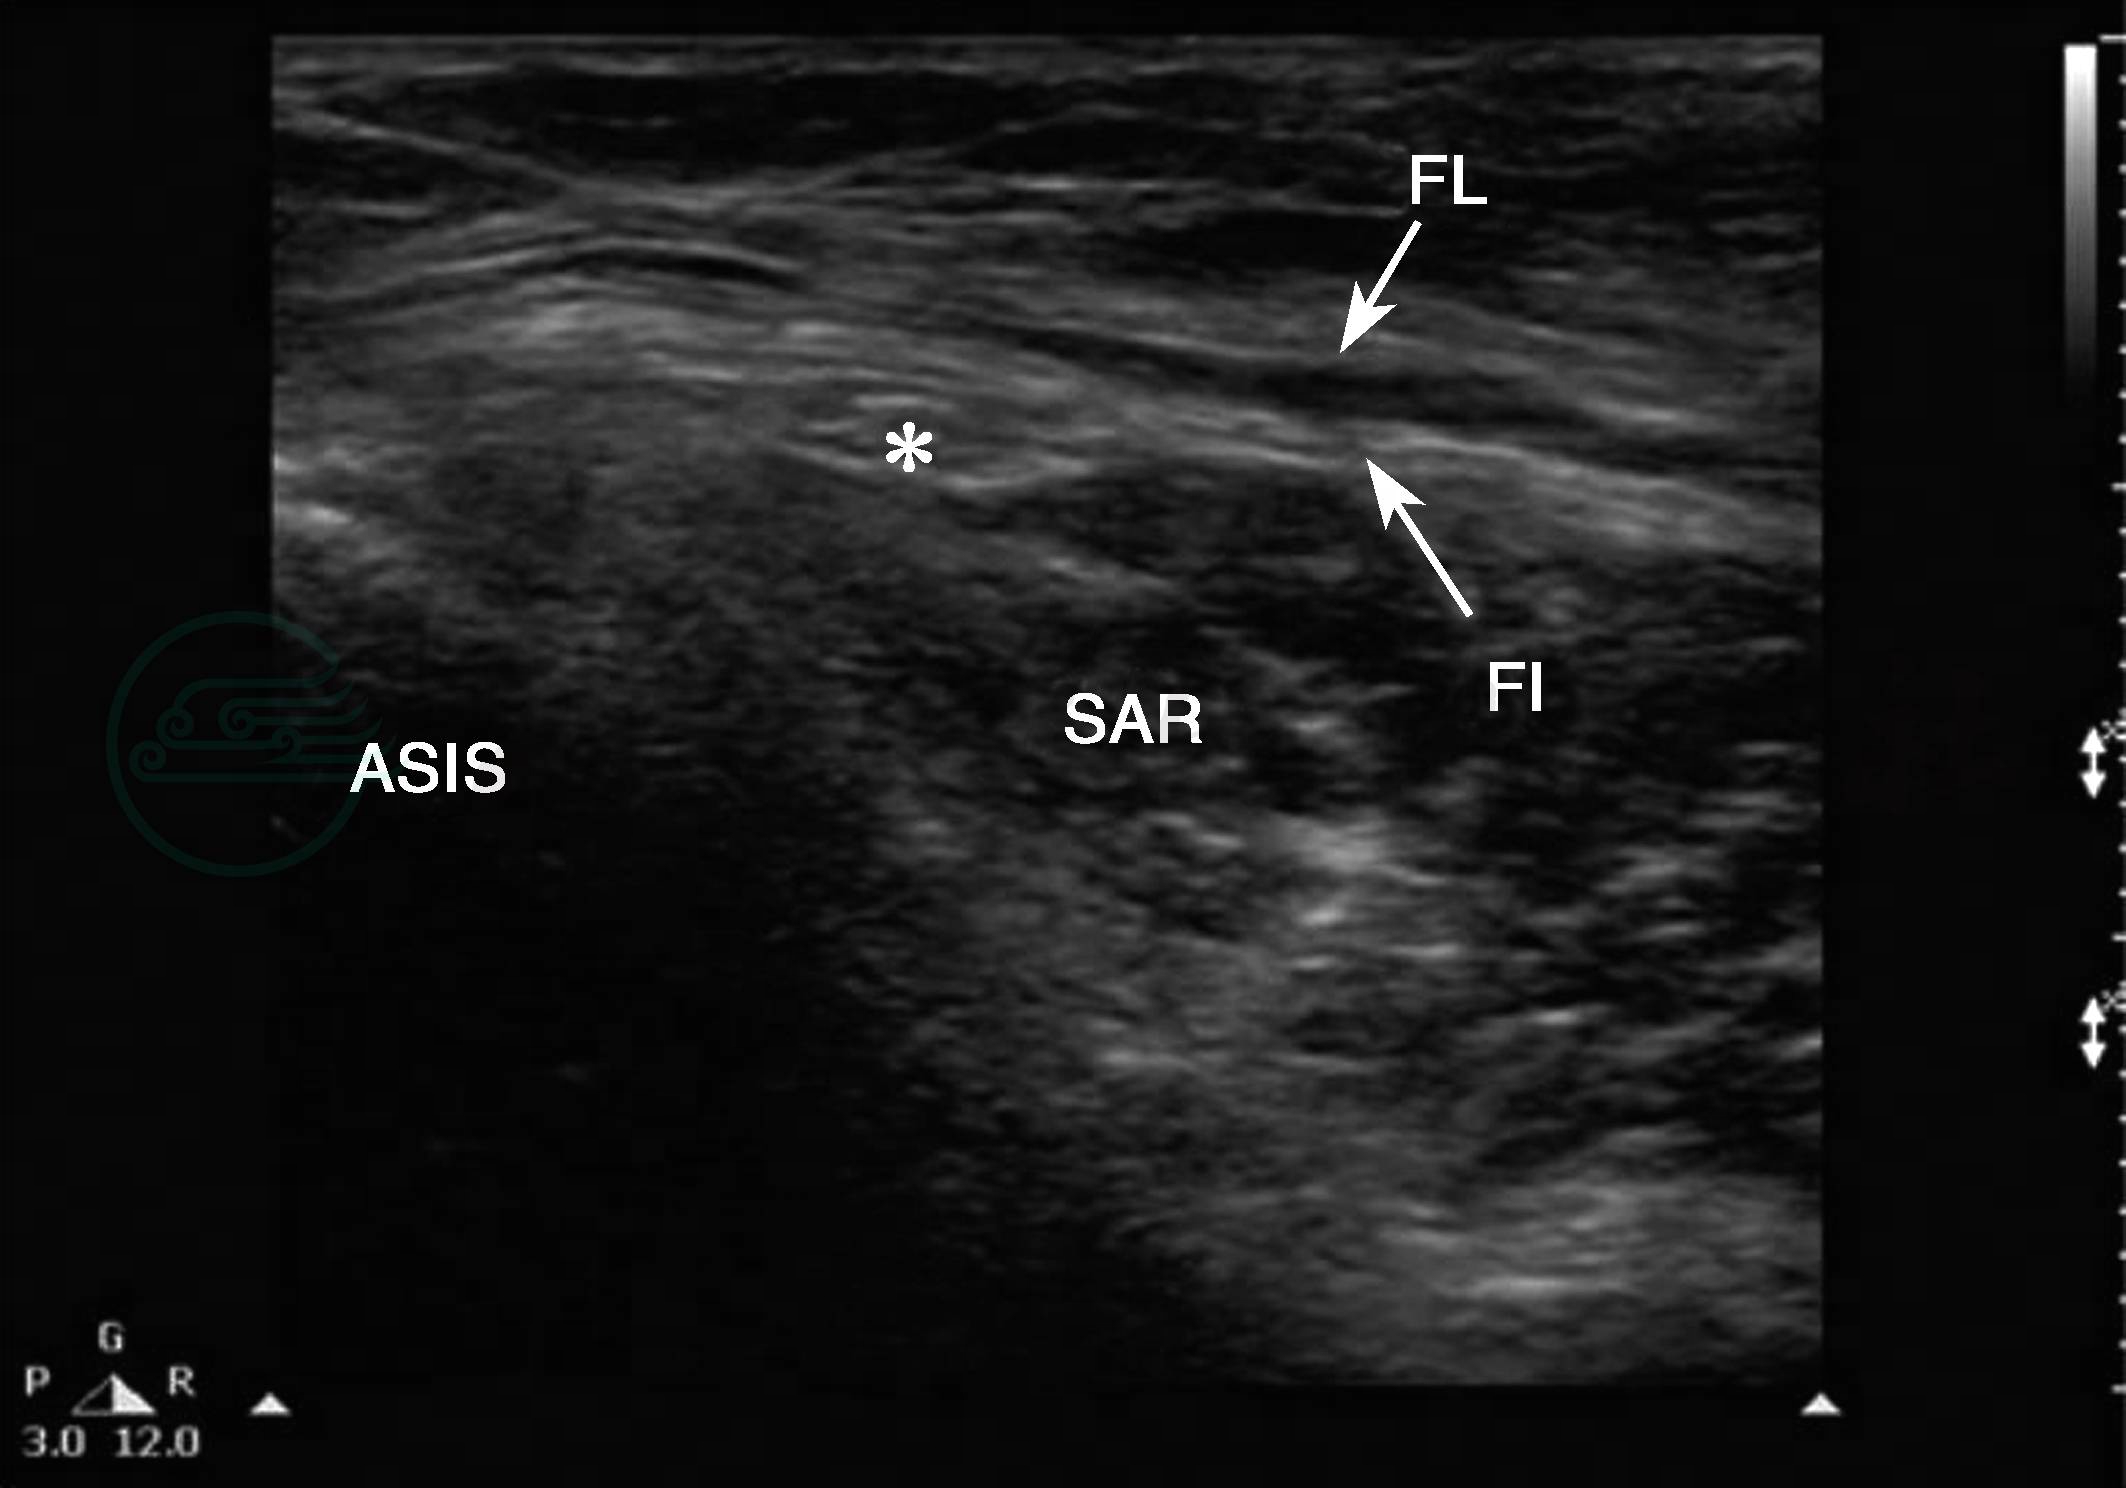

患者仰卧位,将线性高频探头放置于腹股沟韧带上,一侧置于髂前上棘上,另一侧指向耻骨联合,超声可见强回声的髂前上棘,向下方移动探头可见位于阔筋膜与缝匠肌之间的股外侧皮神经呈蜂窝状高回声,内侧可见股动静脉和股神经(图1)。

图1股外侧皮神经超声图

ASIS:髂前上棘;SAR:缝匠肌;FI:髂筋膜;FL:阔筋膜;∗:股外侧皮神经。